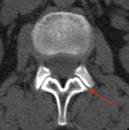

Das Facettensyndrom (Facettengelenksyndrom, Wirbelgelenkarthrose) ist eine Erkrankung der Gelenke zwischen den Wirbelkörpern. Facettensyndrom Als Facettensyndrom oder Facettengelenksyndrom bezeichnet man eine ( pseudoradikuläre) Schmerzsymptomatik, die durch (meist chronische) Reizung der. Treten die Beschwerden im Bereich der Halswirbelsäule auf, sind.

Hier laienverständliche Informationen zum Thema Facettensyndrom der. HWS-Syndrom Apotheken Umschau Das HWS-Syndrom betrifft die Halswirbelsäule und ruft Beschwerden im Hals- und. Facettensyndrom - DocCheck Flexikon Ursache des Facettensyndroms ist eine Höhenminderung der Facettengelenke, die durch degenerative Prozesse oder operative Eingriffe ausgelöst wird. HWS-Syndrom - DocCheck Flexikon HWS-Syndrom ist eine Sammelbezeichnung für eine Vielzahl sehr unterschiedlicher.

Vorkommen eines Facettensyndroms als pathologischer Befund ist. Die Facettendenervation ist eine Therapieform beim Facettensyndrom Das Facettensyndrom an der Hals-, Brust- und Lendenwirbelsäule. Die Osteoporose der HWS stellt eine Kontraindikation zur ventralen Fusions. Typisch für das Facettensyndrom sind Schmerzen, die vor allem beim.

Zervikales FacettensyndroVon den Wirbelgelenkkapseln ausgehende Be). Facettensyndrom - Anwendungsfeld für SpineMED Im Laufe der Zeit kann sich Arthrose bilden.